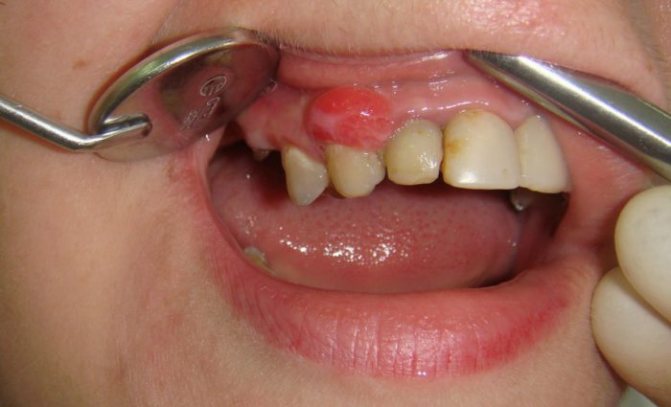

Как выглядят

Папилломы представляют собой небольшое новообразование круглой формы с маленькой ножкой и широкой поверхностью. Их размер, как правило, не превышает 2 см, однако в запущенных случаях этот показатель может увеличиваться. Цвет папилломы обычно бледно-розовый или телесный. Слизистая оболочка не меняет свой цвет, однако в некоторых случаях может становиться более бледной. Это происходит из-за ороговения эпителия. Внешние травмы, например, прикусывание, может спровоцировать изменение цвета папилломы на более темный из-за происходящего кровоизлияния.

При прощупывании нароста больной не чувствует боли, его самочувствие, как правило, нормальное. Если папилломы постоянно травмируются, на них могут возникать изъявления, говорящие о возможности появления онкологии.

- Папиллома на десне. Такая разновидность обычно не доставляет владельцу неудобств и может быть долгое время незамеченной. Однако нарост может травмироваться во время чистки зубов, что в дальнейшем приведет к негативным последствиям.